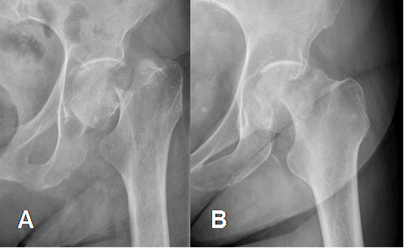

Fig 47. Fractura.

A: Rx AP. Línea radiolúcida en la cabeza femoral, sugestiva de fractura.

B: RM coronal en T1 y C: RM coronal en STIR. Edema óseo en la cabeza femoral, con imagen hipointensa y en sentido oblicuo, que corresponde a fractura.